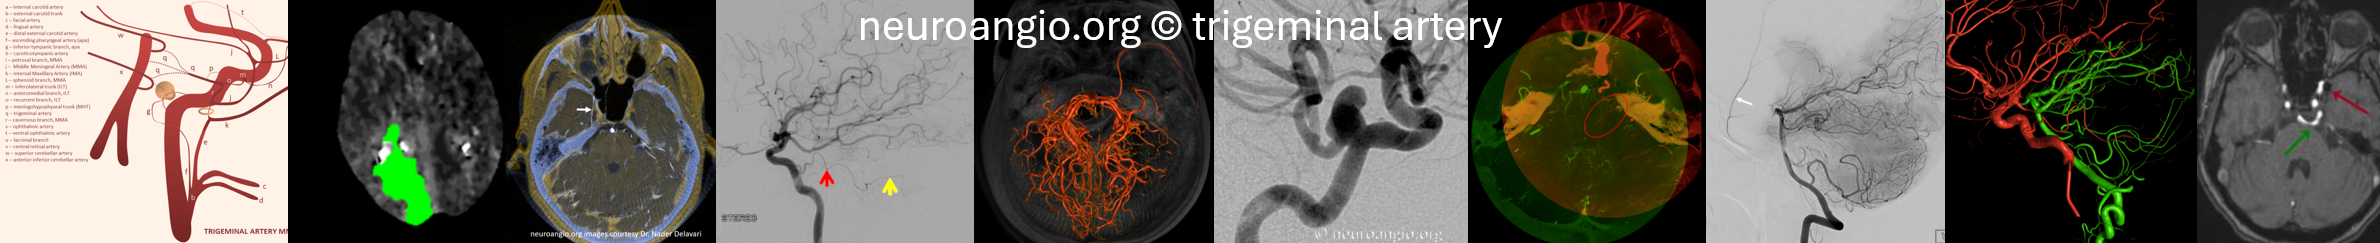

Here are 2D-DSAs

AP view of carotid injections showing the AICAÂ (black arrow), with corresponding wedge-shaped void of its territory seen on the right vert injection. Â Notice fetal disposition of both PCOMs.